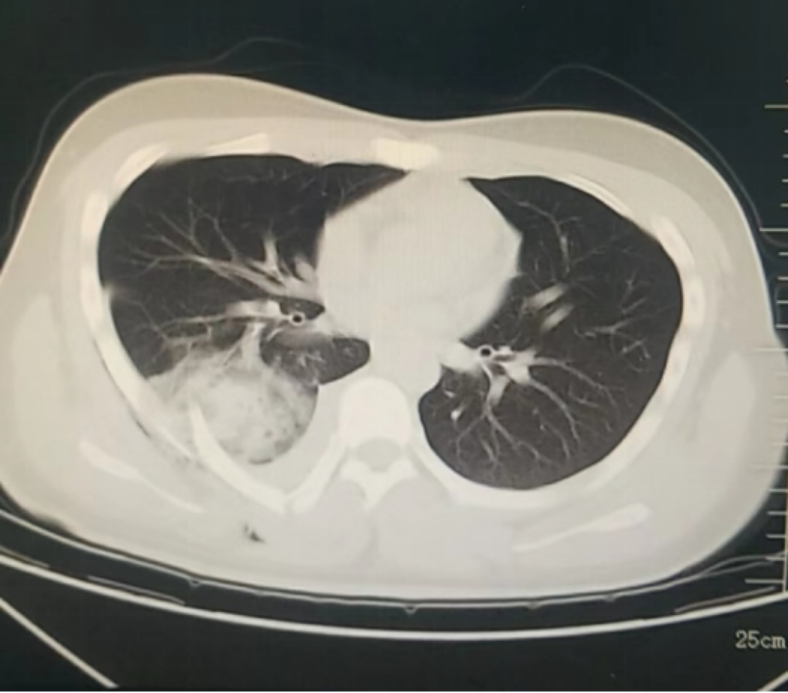

12月26日傍晚,ac米兰官网中文网站四院松北院区胸外科医生办公室响起了急促的电话铃声,松北院区急诊科请求紧急会诊一位“特殊”的外伤患者。受伤的小伙子小杨(化名)是一名在校大学生,从小在广州长大,初次来到哈尔滨被冰雪游乐项目吸引,在玩雪圈快速下滑的过程中,不慎背部受到重击,疼痛难忍。医生在电脑上调出电子胶片,不禁心头一惊,患者由于外伤导致右背侧肋骨骨折,恰好有一根断裂的肋骨像“匕首”一样刺入了右肺下叶,出现了严重的血气胸,如果不马上手术,随时可能出现失血性休克,情况十分危急。医院为患者开通绿色通道,救治工作有条不紊地进行。手术非常顺利,仅60分钟左右。在医护人员的护送下,小杨安全地回到了胸外科病房。第二天,小杨已经能够坐起来了,小杨父母紧紧握住医生的手,感激之情难以言表。